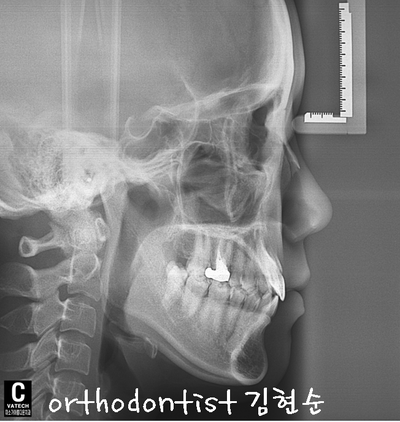

- Treatment plan -

-

치아 사이 공간 해결, 상실 공간 보철 위한 비발치 교정

#42 치아 공간을 벌리고 보철해야 좌우 대칭과 교합이 맞음

상하 교정 장치 부착 → #42 open → 교정 마무리 시기에 implant

예상 교정 기간 약 7 ~ 9 개월